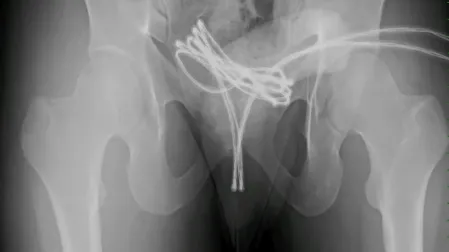

Los estudios de imagen revelaron que el cable había alcanzado su vejiga, lo cual dificultó el procedimiento de extracción. Los médicos optaron por realizar una intervención quirúrgica bajo anestesia general, utilizando una cámara insertada por la uretra para poder retirar el objeto con el menor daño posible.